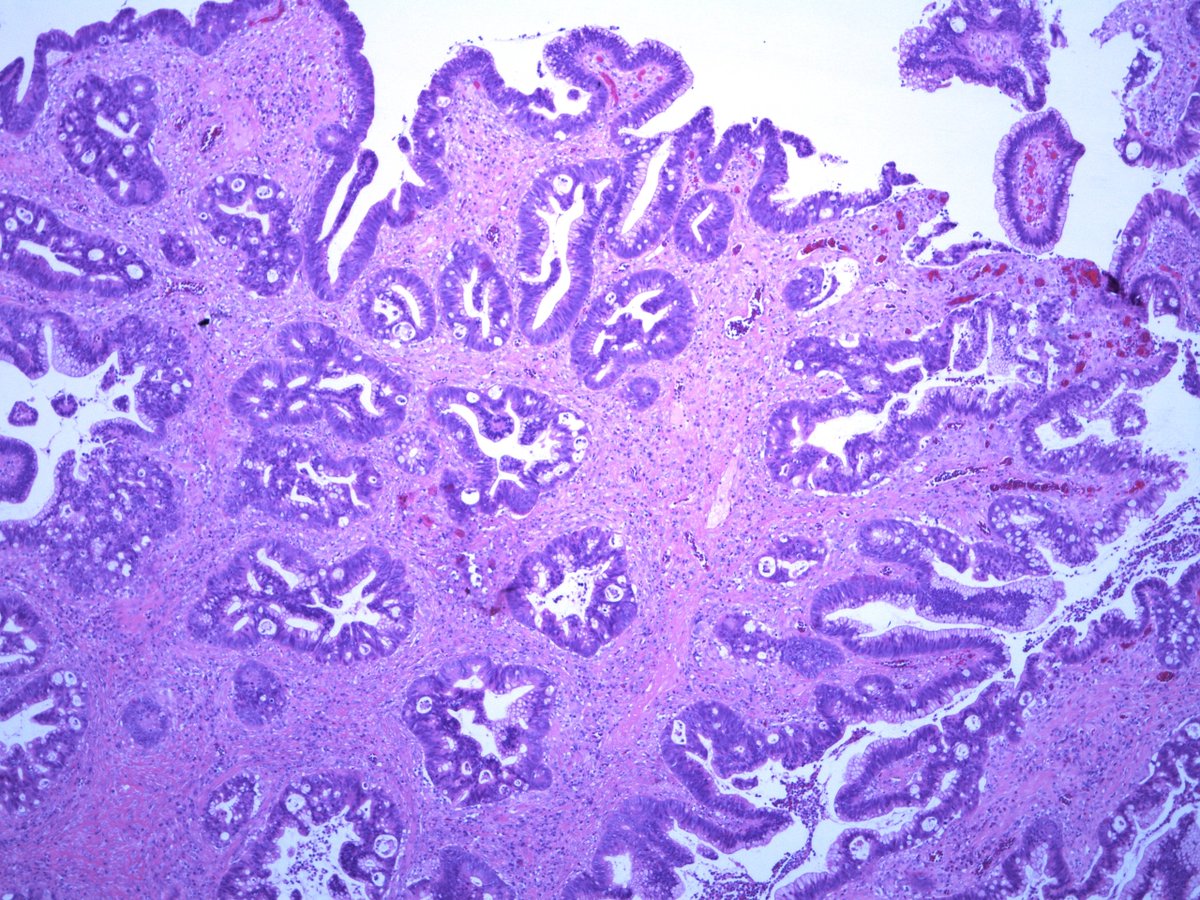

Dear Tweeples, help please. 20mm polyp in sigmoid colon in a background of longstanding mildly active IBD . Is it DALM? Is it Sporadic adenoma? How would you grade it? Any ancillary tests that may add value ? #GIpath #pathologyresidents .more images. @RunjanChetty @MAHoureih